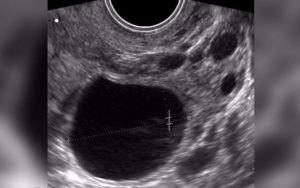

Также назначают фолликулометрию — процедуру, которая включает УЗИ-диагностику в течение всего цикла. Это позволяет отследить работу яичников в каждой фазе.

- Фолликулометрия – процедура УЗИ-диагностики, во время которой ежемесячно отслеживается весь процесс работы яичников в течение менструального цикла.

На фото показан доминантный фолликул. Бывает, что его просто нет, и он не производится от цикла к циклу.

Проблему с появлением доминирующего фолликула можно выявить при помощи ультразвуковой диагностики.

- УЗИ-диагностики. Процедуру отслеживания работы фолликулов называется фолликулометрией. Диагност наблюдает за процессом работы яичников на протяжении всего менструального цикла. Процедура повторяется в течение ряда циклов.

- Пройти фолликулометрию. Обследование представляет собой выполнение серии УЗИ на всем протяжении менструального цикла.

С начала менструального цикла в обоих яичниках образуется порядка 8-10 вторичных фолликулов. Примерно с восьмого или девятого дня цикла пузырьки начинают заполняться образующейся под воздействием синтезируемых женским организмом эстрогенов жидкостью. И уже на данном этапе заметен доминантный фолликул: он больше остальных, и это можно увидеть на УЗИ.